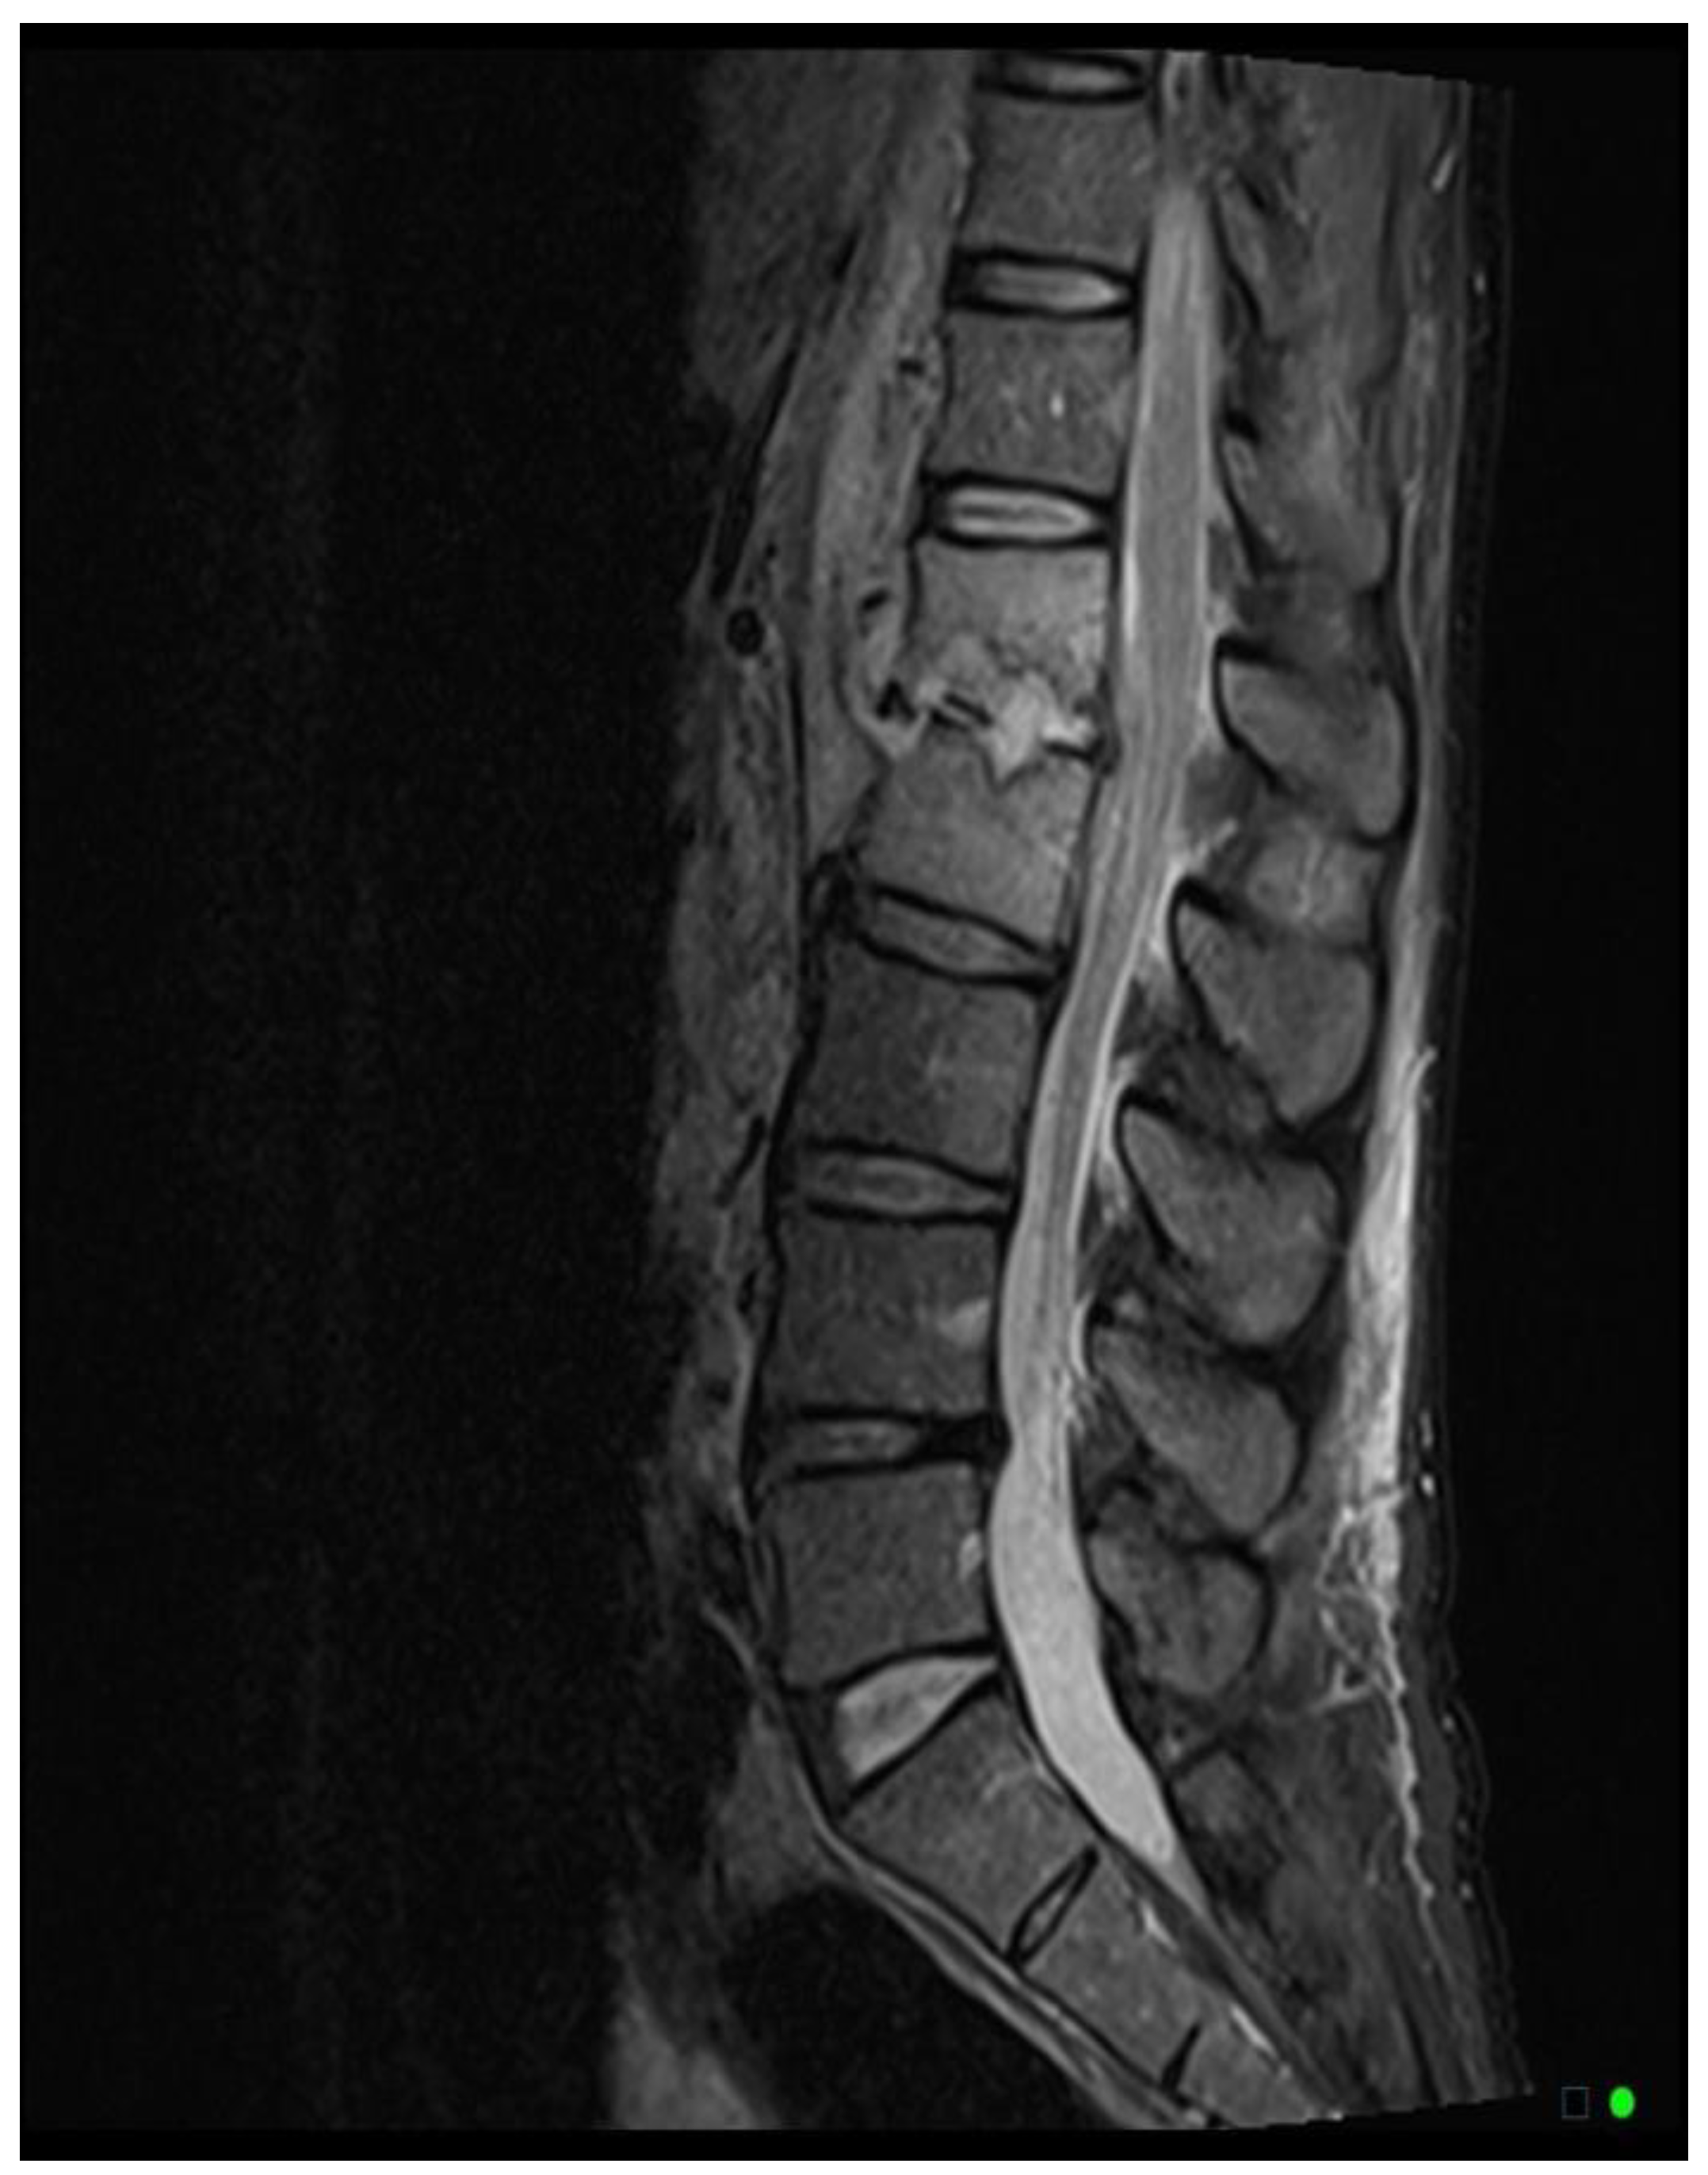

The MRI scoring system utilizes a scale from 1 to 3, with each score representing distinct radiological findings. A score of 1 signifies a hyperintense T2/STIR disc signal, suggesting possible inflammation and edema related to early infection (

Figure 2A). Moving up the scale, a score of 2 denotes both a high disc signal and endplate marrow edema, likely indicative of more advanced stages of VDO (

Figure 2B). Finally, a score of 3 includes high disc signal, endplate marrow edema, and soft tissue edema/abscess, suggesting severe involvement (

Figure 2C).It should be noted that all scoring assessments above were verified using other MRI sequences to improve classification accuracy. For instance, soft tissue edema and abscess can be distinguished from one another using MRI with IV contrast (5). However, differentiating edema from abscess was not necessary for the scope of this study because the presence of either entity could be interpreted as more severe imaging findings related to VDO. Also, as some patients had no MRI with contrast before the biopsy, this approach enabled us to include more patients in our study and simplify the scoring system for greater usability. Thus, we included both soft tissue edema and abscess in the same category, denoted by a score of 3.